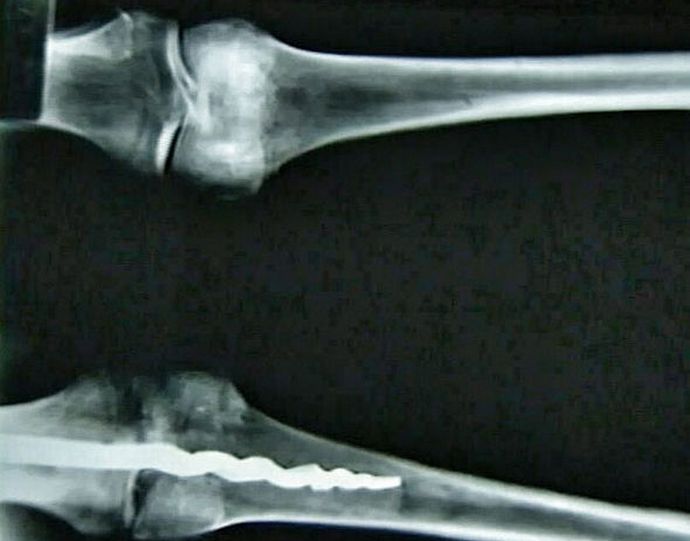

fénykép nyílt forráskódú amerikai kutatók vezetője Egy egyiptomi múmia DNS-elemzése a testében valódinak bizonyult ortopéd tű, a kialakítás nem rosszabb modern társaik. Egyedi leírás hossza 23 centiméter, fémből készült, és a kivitele más feltűnő hasonlóság a gyógyszer ma.

A szakértők szerint az ember térdében ősi sebészek vannak tegye rá a csapot, rögzítve a csontokat, rögzítve ezzel szerves gyanta. Olyan ügyesen csinálták szakmai szempontból a legbonyolultabb művelet nyomot nem hagyott a beteg testén. A felfedezett lelet, módszerek alapján az orvosok által a modern orvostudományban használt régóta őseink előtt ismertek és sikeresen alkalmazzák őket a gyakorlatban.

Még nem ismeretes, hogy ki volt térdben pontosan az egyiptomi amit felfedeztek csodálatos tű. Az amerikai tudósok A Brigham Young University véletlenül látta őt röntgen, majd kivették a testből, kissé meglepve felfedezése.

A talált múmia nem kevesebb, mint 3000 éves, ami azt jelenti, hogy akkor is az ókori egyiptomiak rendelkeztek az építéshez szükséges ismeretekkel csapok, amelyek képesek rögzíteni az elmozdult csontokat a helyesen helyzet és komplex műtéti műveletek elvégzése.

A tudósok még nem tudják magyarázni a titokzatos lelet természetét, megfordította ötleteiket az ősi orvoslásról. Wilfred Griggs, kutatócsoport vezetése, amelynek kezébe került egy egyedi múmia, meggyőződve arról, hogy nem fog sokat adni neki pontosan megtudja, hogyan sikerült létrehozni és elhelyezni az egyiptomi orvosokat az ember teste olyan modern tű.